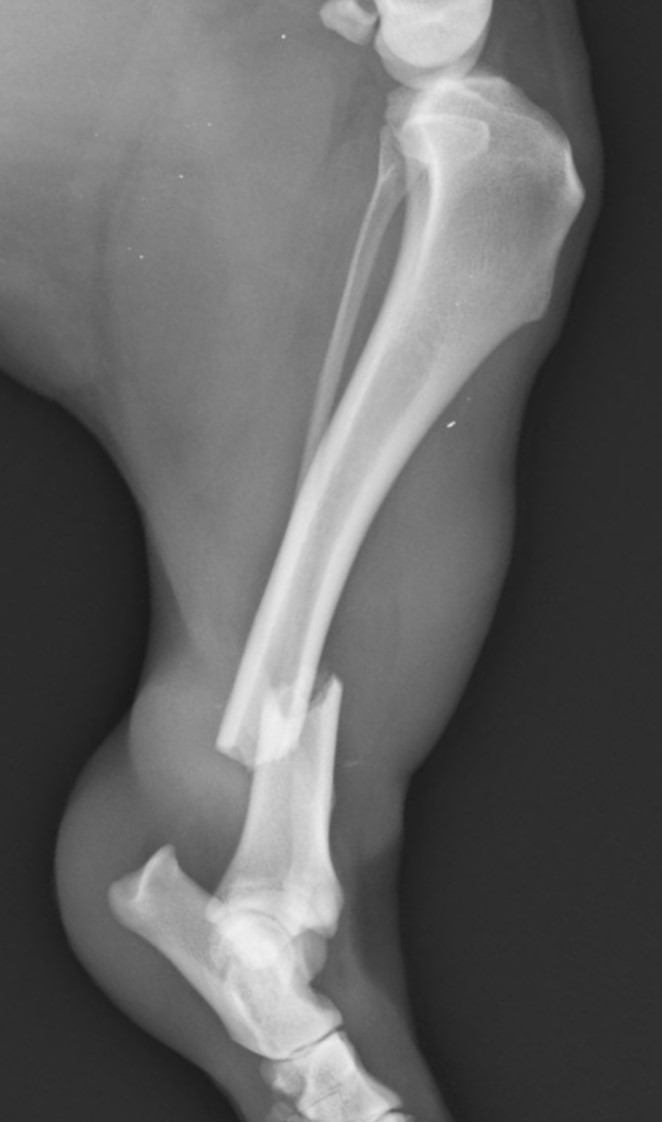

5~6歳以上の去勢手術をしていないオス犬に多い病気ですが、メス犬や去勢した犬に起こることもあります。お尻の筋肉が萎縮した結果、筋肉の隙間から直腸や膀胱が皮膚の下にとびでてしまいます。これにより便が出にくくなったり膀胱炎になったりします。手術をすることで機能回復および今後の致死的な状況を回避することができます。当院では去勢手術→結腸固定→前立腺固定→骨盤隔膜構成筋の縫縮→内閉鎖筋フラップ→浅臀筋フラップの順で通常腹側・臀部左右両側同時に行います。また老化以外に、筋肉が萎縮する原因があったり、腹圧がかかる原因があったりする場合も多いので、再発防止のためそれらの診断・治療も重要です。今回のワンちゃんも無事手術も終わり元気に退院しました。よかったね。